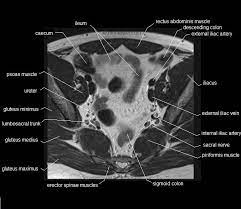

The pelvis is the lower portion of the trunk, located between the abdomen and the lower limbs. Although us, ct and mri may be initially used, pelvic venography is still used to diagnose pvcs and assess the anatomy before treatment is considered. Jun 23, 2021 · the pelvic cavity is described as having two parts: Because of the complexity of this type of injury, a ct scan is commonly ordered for pelvic fractures. This can be done at the same time as ovarian vein/pelvic vein treatment (embolisation) or as a separate procedure if the treatment options need further consideration. In this article, we shall look at the structures of the pelvis, its functions, and the applied anatomy. Abdominal or pelvic adhesions may develop inside the intestine and uterus, or between surfaces of organs and abdominal membrane (peritoneum), thus pulling organs from their original positions, obstructing passage of food and blood supply, causing abdominal or pelvic pain, bloating, constipation, urinary retention, irregular menstrual bleeding. Dec 31, 2009 · surgery stabilizes the injured pelvic ring, restores normal anatomy, provides patient comfort and allows rehabilitation.

It connects the axial skeleton to the lower limbs. Although us, ct and mri may be initially used, pelvic venography is still used to diagnose pvcs and assess the anatomy before treatment is considered. There is a false pelvis that spans the region below the iliac crest and above the arcuate line (pectinate line, anteriorly) and there is a true pelvis that begins below the arcuate line. Types of surgery recommended displaced (misaligned) pelvic fractures may be stabilized by either internal or external fixations (after accurate realignment of the bone fracture fragments or dislocation sites). The pelvis's frame is made up of the bones of the pelvis, which connect the axial skeleton to the femurs, and therefore acts in weight bearing of the upper body. In this article, we shall look at the structures of the pelvis, its functions, and the applied anatomy. The main focus of this article will be the pelvic floor muscles. The pelvis is the lower portion of the trunk, located between the abdomen and the lower limbs. The pelvic inlet or superior aperture of the pelvis is a planar surface which defines the boundary between the pelvic cavity and the abdominal cavity (or, according to some authors, between two parts of the pelvic cavity, called lesser pelvis and greater pelvis). This can be done at the same time as ovarian vein/pelvic vein treatment (embolisation) or as a separate procedure if the treatment options need further consideration. Jun 23, 2021 · the pelvic cavity is described as having two parts: Dec 31, 2009 · surgery stabilizes the injured pelvic ring, restores normal anatomy, provides patient comfort and allows rehabilitation. Because of the complexity of this type of injury, a ct scan is commonly ordered for pelvic fractures.

There is a false pelvis that spans the region below the iliac crest and above the arcuate line (pectinate line, anteriorly) and there is a true pelvis that begins below the arcuate line. Jun 23, 2021 · the pelvic cavity is described as having two parts: As a result, spaces associated with. Jun 17, 2021 · the pelvic floor is primarily made up of thick skeletal muscles along with nearby ligaments and their investing fascia. Because of the complexity of this type of injury, a ct scan is commonly ordered for pelvic fractures. The main focus of this article will be the pelvic floor muscles. The caudal end of the peritoneal cavity rests in the pelvic cavity. The pelvis is the lower portion of the trunk, located between the abdomen and the lower limbs.